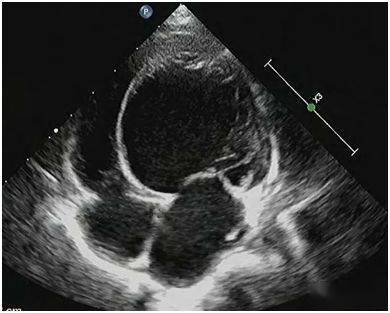

彩色多普勒超声诊断胎儿心脏多发性肿瘤1例 大,心内膜弹力纤维增生